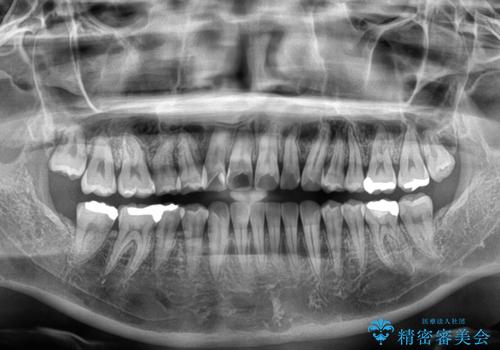

上下前歯のデコボコを気にして来院された患者様です。

ワイヤー矯正でもマウスピース矯正でも可能でしたが、短期間で、自身の手を煩わせることなく治療を行いたいとのことで、ワイヤー装置にて矯正治療を行うこととしました。

舌の突出癖により、治療過程でスペースが多くできましたが、舌のトレーニングを頑張っていただき、1年強で終えることができました。